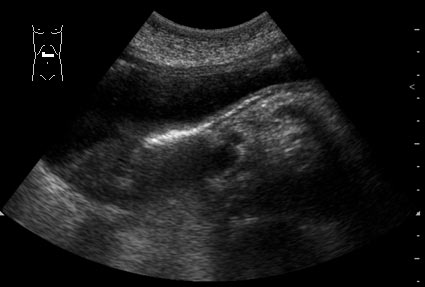

Мужчина 55 лет поступил в приемный покой БСМП с клиникой язвенного кровотечения.

При УЗИ выявлены изменения стенок желудка (см сонограммы)

Так, уважаемые коллеги. Утолщения стенок желудка там нет. Содержимое в пилорическом отделе акустически непрозрачно, -"кисель". Постараюсь найти другие сканы или даже видео. Обратите внимание на структуру задней стенки.

По данной вашей публикации, сложно высказатся однозначно, к УЗИ ЖКТ, как никогда подходит утверждение: (real time imaging), визуализация в режиме реального времени. Гиперэхогенные включения в виде ленты (ribbon-like echoes) по задней стенке могут оказатся фибрином покрывающим язвенный дефект стенки, а может и нет. Я в таких случаях стараюсь подробно описать УЗ-картину и сразу направляю на эндоскопию.

В данном случае определяется феномен эхоусиления от подслизистой оболочки задней стенки выходного отдела желудка. Возможно, что это вариант нормы, так как задняя стенка находится в зоне усиления. Желательно провести р-скопию и ФГДС, так как эрозивные поражения, которые могут сопуствовать процессу, при УЗИ увидеть практически невозможно.

возможно иннородное тело(если идет речь о сплошной гиперэхогенной структуре по задней стенк.После более пристального просмотра:срединное эхо "занято"средней эхогенности содержимым,которое отграничено позади гиперэхогенной линией-может это сплошной сгусток крови заполняет срединное эхо желудка?(возможно внутри сплошные кровоточащие эррозии)